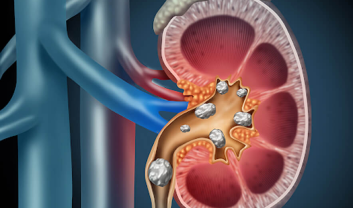

Kidney stones are solid deposits that form in the kidneys when substances like calcium, oxalate, and phosphorus become concentrated.

Ureteric stones, commonly known as kidney stones, can be excruciatingly painful experience for anyone affected by them.